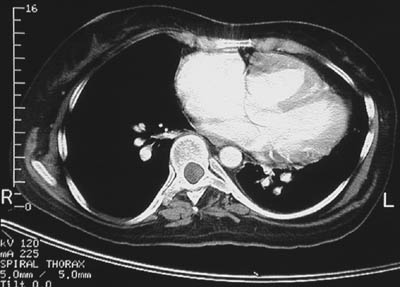

| The chest CT scan above in bone window reveals a discontinuity involving the superior aspect of the interventricular septum. This is consistent with a venticular septal defect that explains the cardiomegaly, particularly of the right ventricle, as seen below in lung window. Over the years, the left-to-right shunt induces increasing pulmonary hypertension, seen as prominent bright pulmonary arteries in the lowest frame below, and the shunt reverses, a so-called Eisenmenger complex. |